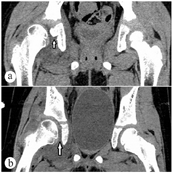

患儿,女,6岁9个月。因步态异常1个月余前来就诊。患儿1个月前摔倒后诉右侧腿痛伴跛行,无发热。查体:患儿跛行,双侧髋关节处未见明显皮肤缺损,右侧股动脉搏动不明显,右侧髋关节外展试验阳性,双下肢基本等长。实验室检查:血沉35 mm/h, C反应蛋白22 mg/L。CT检查示:右侧髋关节脱位,髋臼内形态不规则骨质密度影,血肿机化可疑。初步诊断:右侧感染性髋关节炎。入院后复查:血沉36 mm/h, C反应蛋白24 mg/L,外周血白细胞计数正常,T-spot结果正常,行髋关节穿刺2次,均未抽出液体。查3D-CT显示:右侧髋关节积液伴坐骨支髋臼面骨质异常,考虑感染及右髋关节半脱位。MRI显示:右侧髋关节积液伴周围软组织肿胀,右髋臼诸组成骨骨髓水肿,考虑感染;右髋臼缘下方见小骨片影,髋关节内侧间隙增大。予以抗感染(美洛西林钠舒巴坦钠1.5 g, 8 h 1次,五水头孢唑林钠0.5 g,8 h 1次)治疗1周后,症状无明显减轻,考虑患儿可能为幼年特发性关节炎,行抗CCP、抗"O"与RF、淋巴细胞免疫分析、体液免疫5项(IgA、IgG、IgM、C3、C4)、PCT等相关检查,结果均正常。再次行髋关节穿刺,抽出7 ml淡黄色液体,送检后无阳性结果。复查血沉36 mm/h, C反应蛋白正常。行髋关节穿刺,取黄色浑浊液体2 ml送细胞病理学检查,并查肿瘤4项(AFP、CEA、NSE、CA19-9),结果均正常。患儿经抗感染治疗28 d后,症状无好转,复查血沉28 mm/h。再次复查MRI,结果无明显改变,结合之前影像检查,诊断为:儿童髋关节剥脱性骨软骨炎,予以手术探查。术中发现右侧髋关节囊水肿明显,关节呈半脱位状态,关节内有约15 ml淡黄色清亮液体。髋臼内后方可见约0.5 cm×0.5 cm×0.5 cm大小软骨块突起于髋臼软骨表面,旁边可触及约1.0 cm×1.0 cm软骨面缺损。清除病灶后复位髋关节,术后髋上支架固定6周后脱架。术后病理报告:送检组织内可见增生的纤维组织、骨小梁、骨样组织,少量软骨及肉芽组织,其间见多量扩张的血管,局部伴出血,见慢性炎症浸润。结合影像学及临床表现符合儿童剥脱性骨软骨炎。术后患儿发热2 d,热峰38 ℃,C反应蛋白14 mg/L,血沉91 mm/h,予以对症处理后,均恢复正常,术后1个月患儿疼痛症状消失,复查CT、MRI等均见髋关节呈头臼同心圆结构,软组织肿胀消退(图1、图2)。予以出院,1年后随访患儿髋关节无不适,活动正常。

注:a术前,b术后。